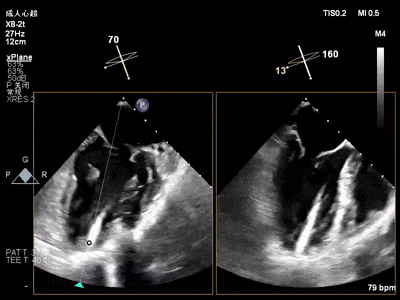

术中超声(关键步骤)

术前术后对比图

术前

术后

术后,出院检查报告显示夹子位置固定,无移位,二尖瓣轻度反流,左室大小和LVEF值正常范围,左室壁运动分析未见明显异常。